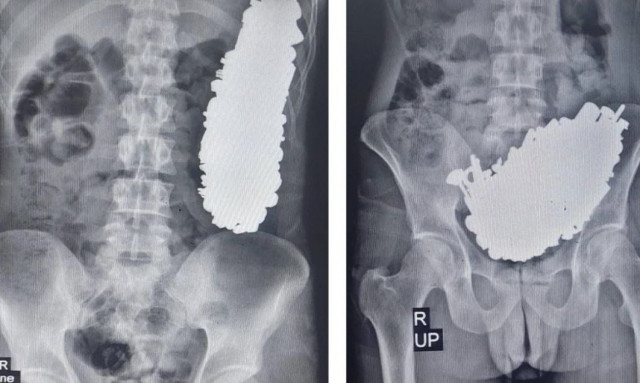

Απίστευτο: Άνδρας είχε καταπιεί 450 μεταλλικά αντικείμενα - Τι αναφέρουν οι... χειρουργοί

Απίστευτο: Άνδρας είχε καταπιεί 450 μεταλλικά αντικείμενα - Η περίπτωσή του έγινε επιστημονική μελέτη

Μετά την επιτυχή επέμβαση αφαίρεσής τους, οδηγήθηκε σε... ψυχιατρείο.

Φρίκη: Κατάπινε ξυραφάκια, καρφιά, νομίσματα και δε μπορούσε να σταματήσει - Σοκαρισμένοι οι γιατροί

Γάλλοι χειρουργοί αφαίρεσαν από το στομάχι ενός άνδρα περισσότερα από 100 κομμάτια μετάλλων διαφόρων σχημάτων και μεγεθών, τα οποία είχε καταπιεί λόγω ψύχωσης.